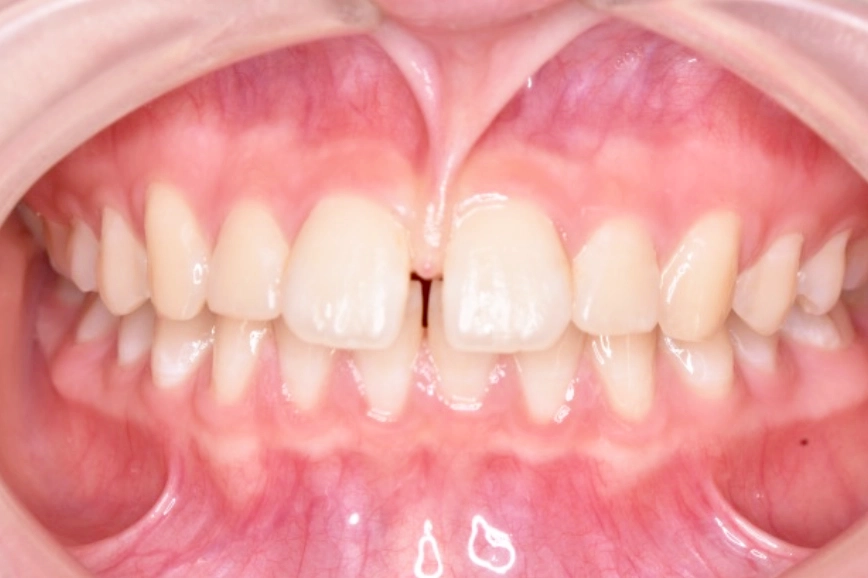

マウスピース矯正の症例

治療前

治療中

治療後

| 治療名 | 上唇小帯切除術、 アライナー矯正治療 |

| 患者様情報 | 10代 女性 |

| 担当医 | 高橋 隼平 先生 |

| 費用 | 800,000円 (税込) |

| 主訴 | 見た目が気になっている。上の前歯は歯ブラシが当たると少し痛い。 |

| 治療期間 | 約1年6ヶ月 (約2~3ヶ月に 1回ペース) |

| 治療内容 | 見た目が気になり、上の前歯は歯ブラシが当たると少し痛いとのことで来院されました。 上唇小帯については、上唇小帯切除術し、傷口が治癒した後は、インビザラインにて矯正治療を行いました。 |

| 治療のリスク | 矯正治療後、保定装置をしっかり使わないと後戻りする可能性があります。 |